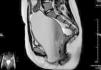

Dados los hallazgos, se realizó una RM pélvica para descartar otras anomalías del tracto urogenital y confirmar nuestra sospecha diagnóstica.

La RM describió una gran dilatación de la cavidad vaginal, con unas medidas totales de 150×80×82mm (Cc×Ap×LI), que presentaba contenido líquido heterogéneo (probable secreción y sangre) y que ejercía un efecto masa sobre la vejiga urinaria. El útero se encontraba desplazado cranealmente, situándose a nivel de L4-L5. Los 2 anejos eran de morfología normal (figs. 1 y 2).